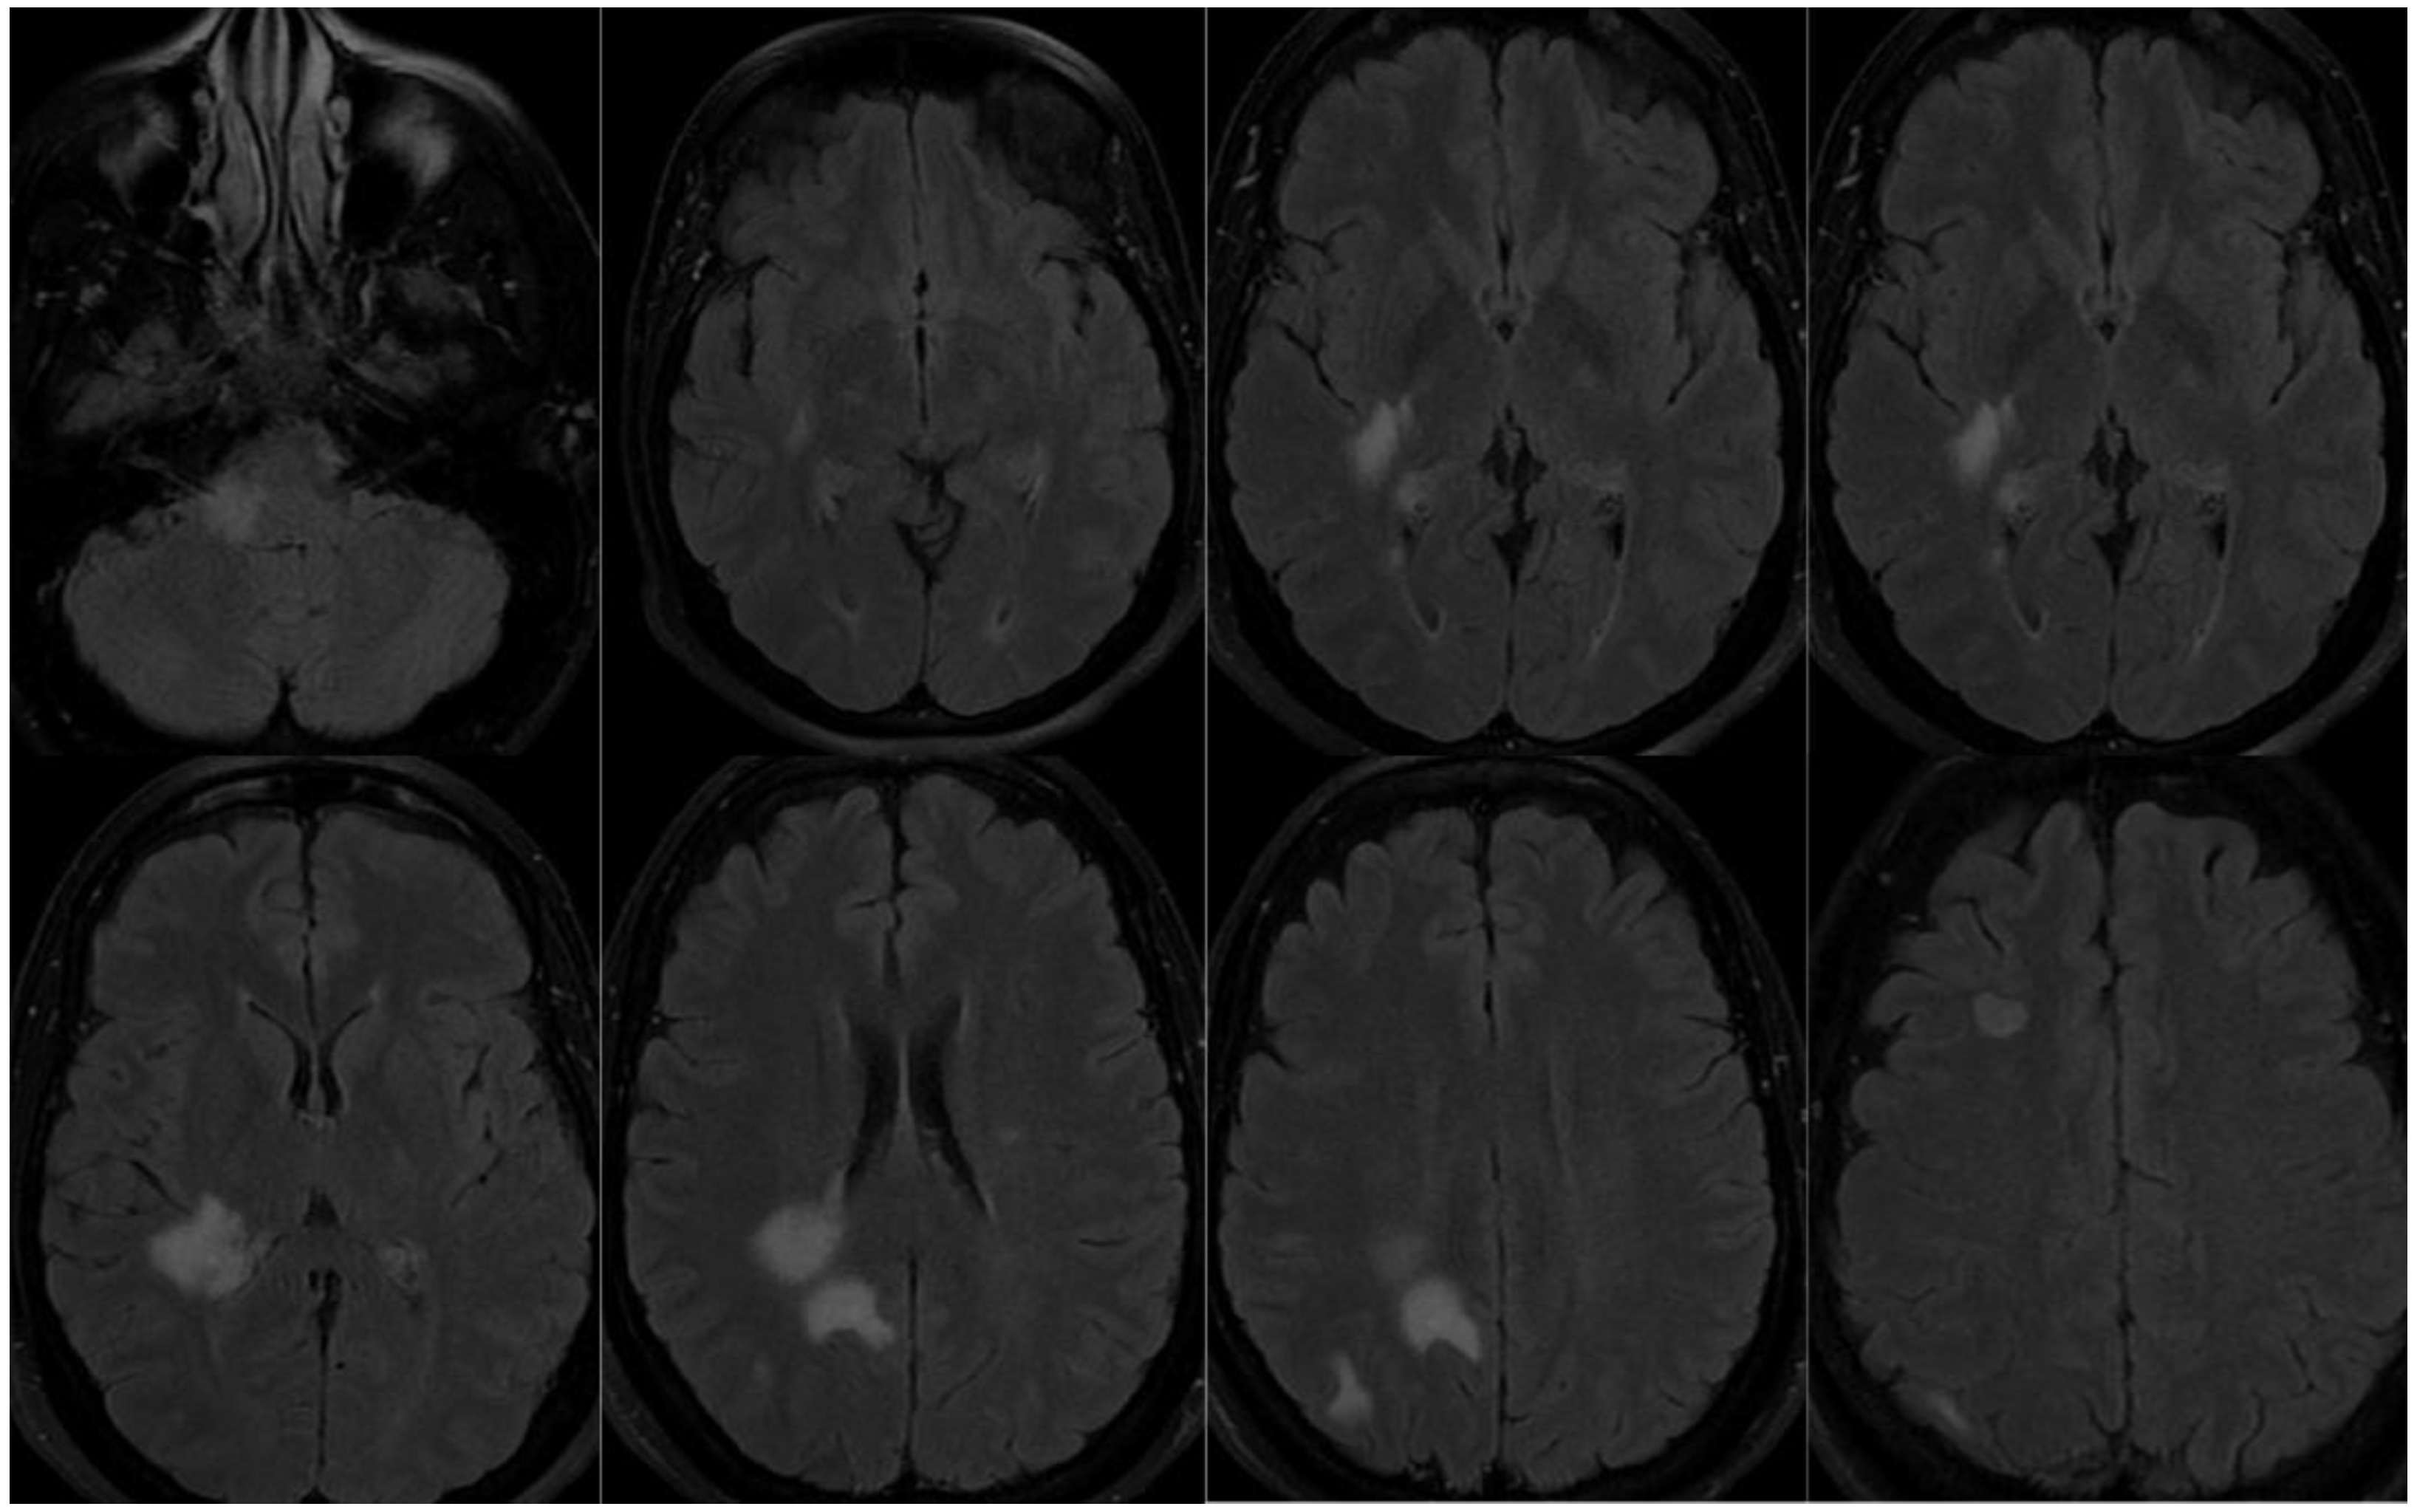

3.1.1. Patient 1

3.1.2. Patient 2

3.1.3. Patient 3